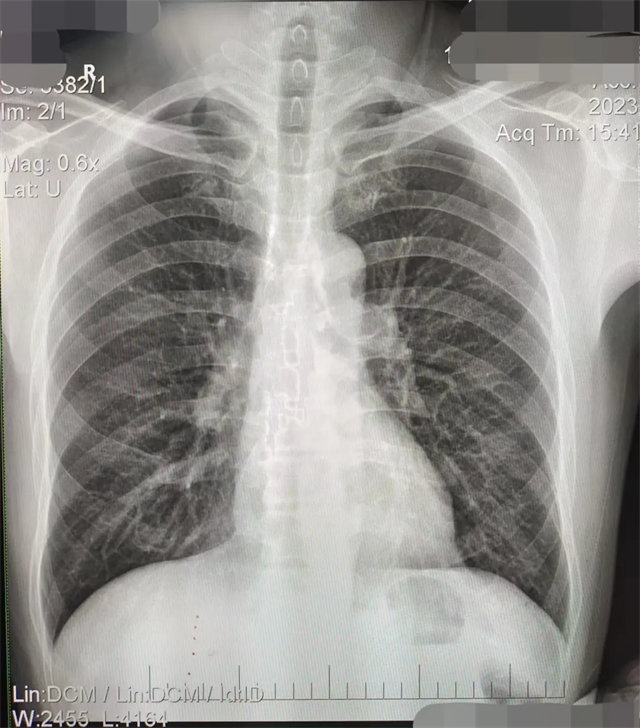

缺陷:兩肩胛骨未拉開肺野之外,吸氣不完全,且存在金屬飾品遮擋。

解決:去除金屬飾品及內衣后重新按標準體位攝片即可。